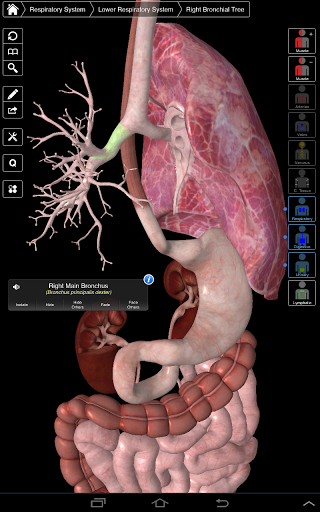

Essential Anatomy 3 represents the latest in groundbreaking 3D technology and innovative design. A cutting edge 3D graphics engine, custom built by 3D4Medical from the ground up, powers a highly-detailed anatomical model and delivers outstanding quality graphics that no other competitor can achieve.

The app represents a unique approach to learning general anatomy. The graphics are unparalleled and make learning, through the use of informative content and innovative features, a rich and engaging experience.

⁃Respiratory

⁃Digestive

Essential Anatomy 3 is responsive, visually stunning and effortless. The app is fully 3D, meaning that you can view any anatomic structure in isolation, as well as from any angle.

---- Over 4,000 highly detailed anatomical structures

---- Latin nomenclature for each anatomical structure